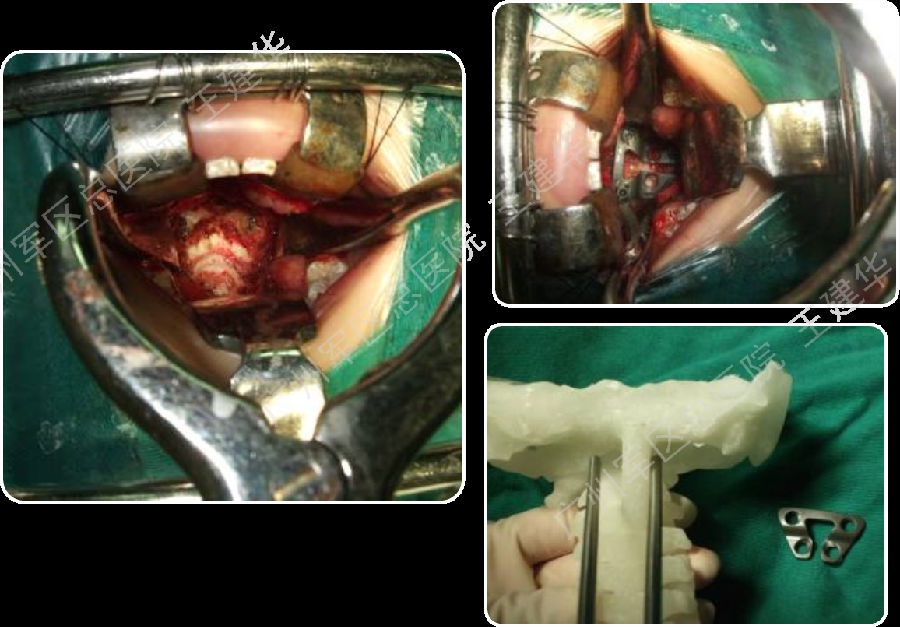

术前术后对比

病例2

术前诊断

如何手术?

本例患者手术过程

手术前后对比

手术后CT显示,陷入枕骨大孔的齿突获得下拉复位

术后MRI发现,患者的颅底凹陷,脊髓空洞和Chiari畸形均获改善